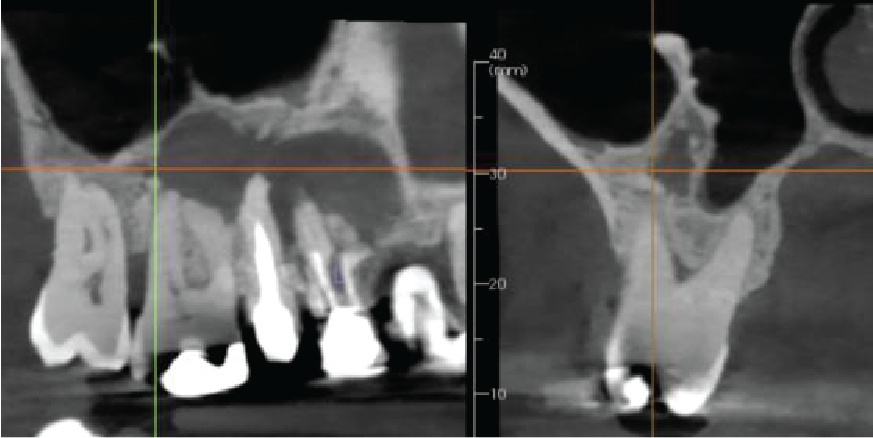

There is apical pathology on the UR6,5,4. The UR6 buccal roots have a large apical radiolucency. The UR4 and UR5 are root treated with large apical radiolucencies and destruction of the buccal cortical plate. These are probably apical granulomas or radicular cysts secondary to chronic apical periodontitis. They are contiguous and measure 12 x 25 x 9 mm.

The right maxillary sinus floor has reactionary bone formation, almost certainly due to the chronic inflammation from the apical disease. However, there is no thickening of the sinus mucosa.

Cropped panoramic and cross section of the alveolar ridge in the UR4-6 region showing chronic apical infection and reactionary bone formation in the right maxillary sinus

Cropped panoramic, axial and cross sections of the alveolar ridge UR4 6 region showing chronic apical infection